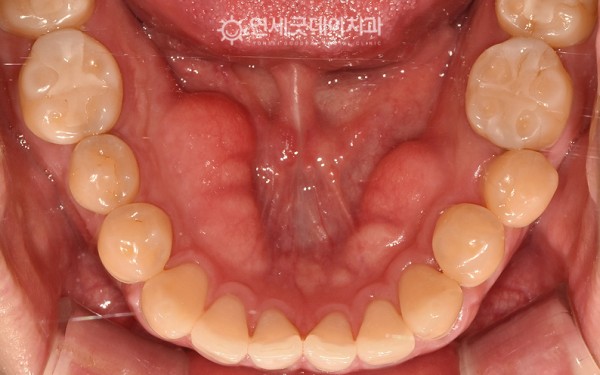

10일 후 경과체크를 위해 내원하셨을 땐

토러스 제거부위가 잘 아물고 있었습니다.

대부분 1~2주 내로 완전히 힐링되어

매끈한 잇몸으로 회복하실 수 있답니다.